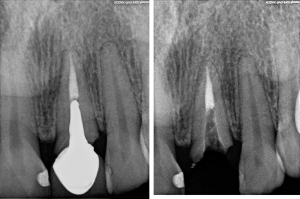

Antes del diente en deterioro con infección

Antes: paciente con dos dientes frontales ausentes con pérdida de hueso y encía. 7 años después de colocación de implantes con injerto de hueso y encía